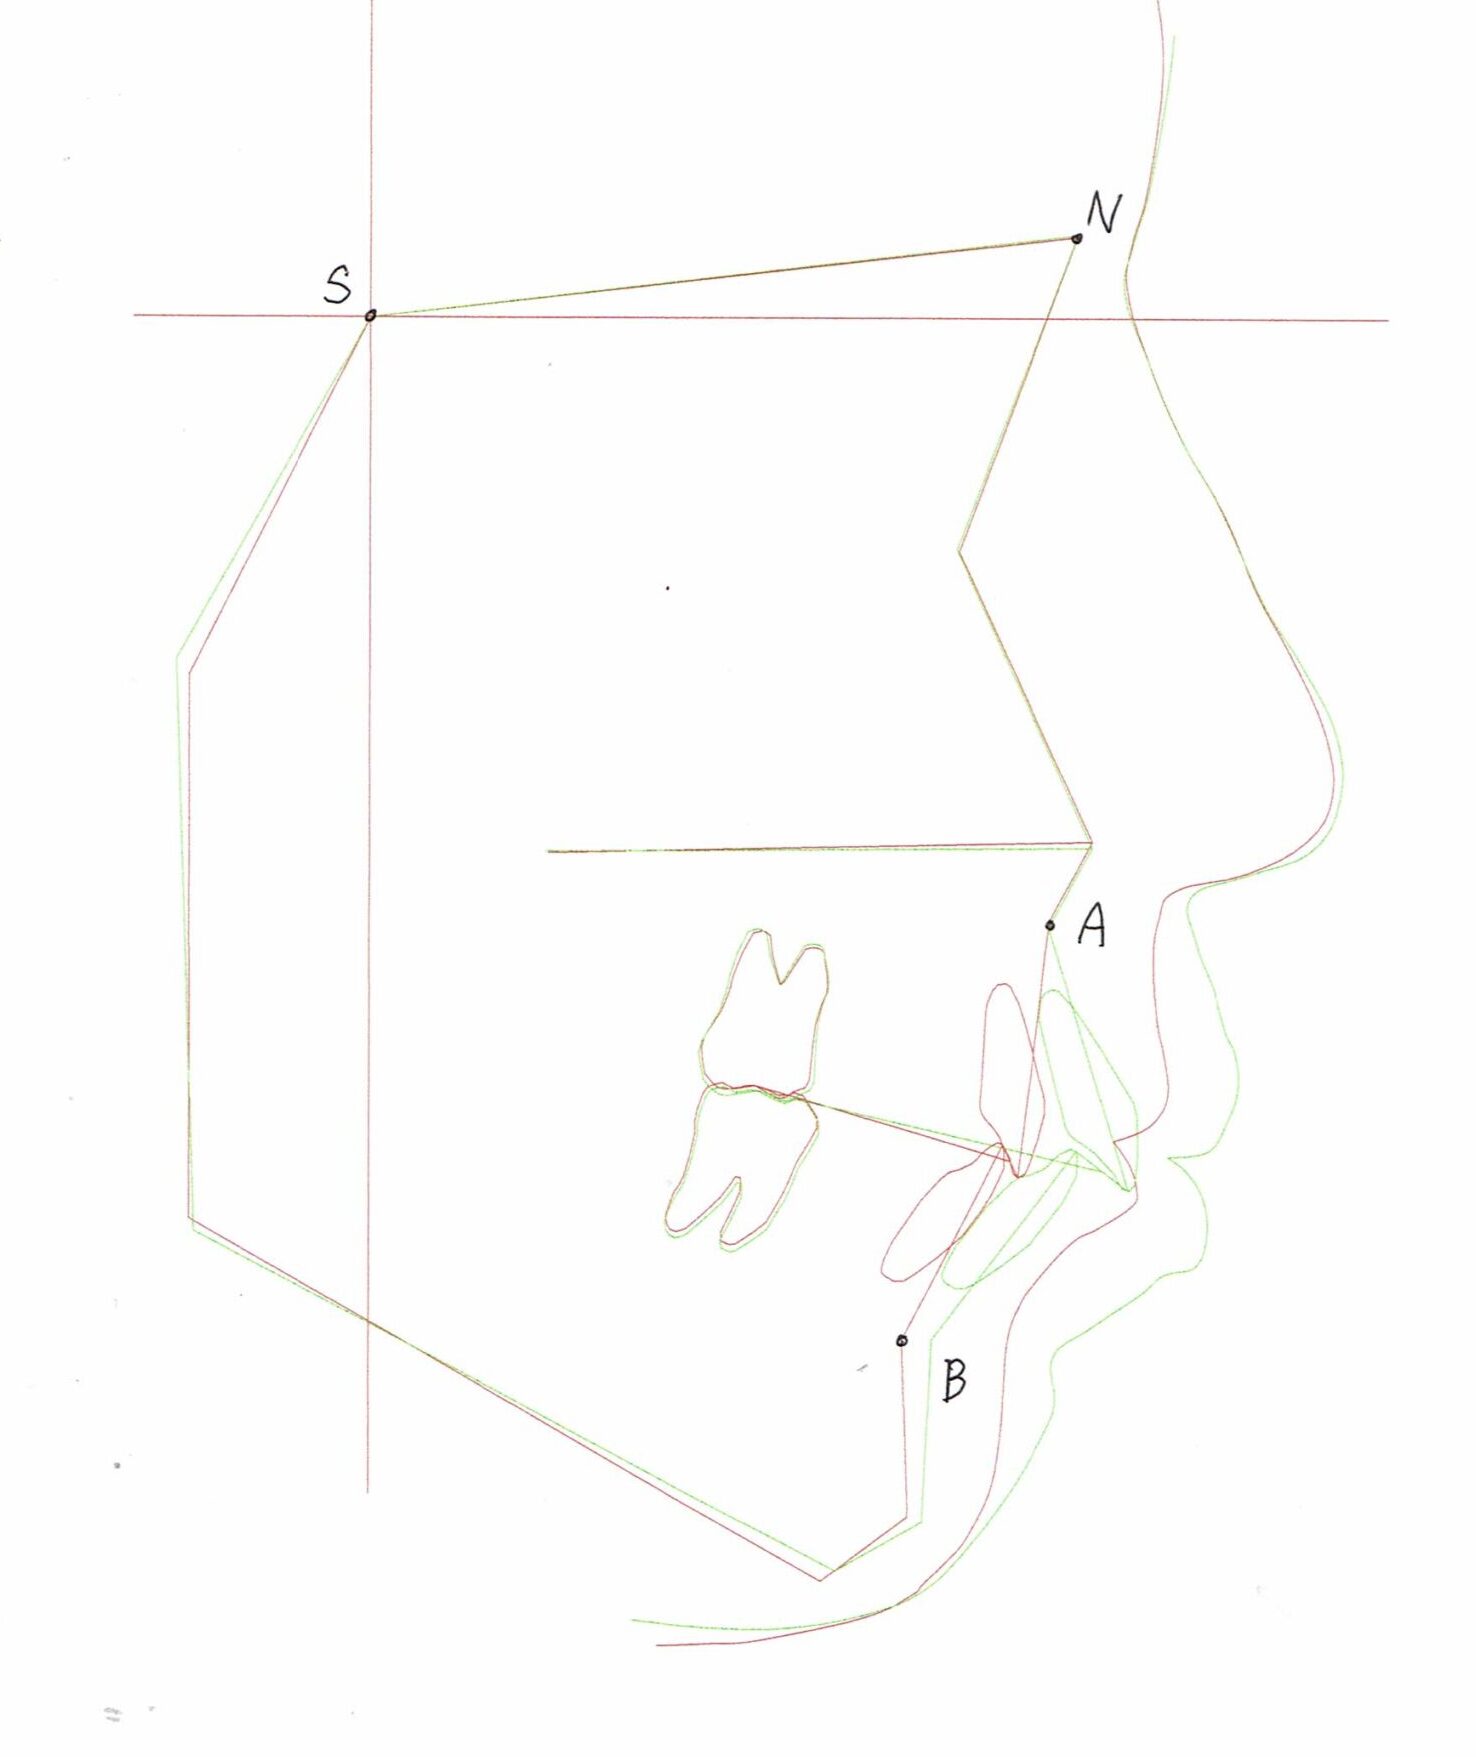

セファログラムのトレースの重ね合わせ(緑:治療前、赤:治療終了時)

治療前後の解説

| 治療前 | でこぼこしている歯による歯磨きのやりにくさや、奥歯がしっかり咬んでいない鋏状咬合(すれ違い咬合)。 出っ歯による口の閉じにくさ(口唇閉鎖不全)と、正面から見た時のオトガイ部にできる梅干し様のシワやイーラインから飛び出た口元(口ゴボ)。 機能面も審美面も気にしていた患者さんです。 治療中もなるべく装置を目立たせたくないため、ハーフリンガルでの治療となりました。 |

| 治療後 | 上下の歯がお互いにはまり込み、全体的に緊密な咬み合わせになっています。 出っ歯が治り、口元の突出感が改善されて綺麗なEラインを獲得しました。 すれ違い咬合や叢生(歯のでこぼこ)も治って歯磨きがしやすく、嚙みやすい状態になっています。 |